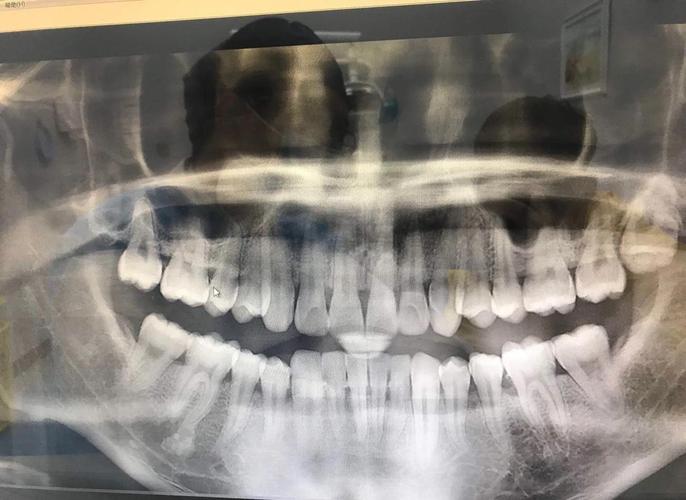

| 全景片(曲面断层片) | 观察全口牙齿排列、牙根形态、牙槽骨高度、第三磨牙位置、颌骨病变及发育情况 | 优点:辐射低(约0.007mSv)、费用低、可显示全口牙列;缺点:二维重叠、细微结构模糊 | 常规正畸初筛,了解牙齿数目、萌出顺序、牙根有无吸收、牙槽骨整体状况 |

| CBCT(锥形束CT) | 三维重建颌骨、牙齿、神经血管位置,清晰显示埋伏牙方向、牙根与骨皮质关系、上颌窦及下颌管位置 | 优点:三维立体、分辨率高、可任意角度旋转;缺点:辐射高于全景片(约0.1-0.3mSv)、费用高 | 复杂病例(如埋伏牙牵引、正颌手术术前评估、骨量不足需植骨者、颞下颌关节紊乱检查) |

正畸医生需结合全景片、头颅侧位片、CBCT等多源影像,结合临床检查(模型、口内照、面部分析)进行综合解读,对于“牙列拥挤”患者,全景片需观察牙根有无弯曲、吸收,牙槽骨高度是否支持牙齿移动;头颅侧位片需分析拥挤是否由颌骨发育不足(如上颌骨狭窄)导致,以决定是否需要扩弓或拔牙矫治,CBCT则可明确牙槽骨厚度,判断隐形矫治附件粘贴的可行性,或正颌手术中骨块移动的安全范围。

A:全景片虽能显示全口牙列,但属于二维重叠影像,对埋伏牙、牙根与骨皮质关系、颌骨内重要解剖结构(如下牙管、上颌窦底)的显示存在局限,CBCT可三维重建颌骨和牙齿,清晰呈现埋伏牙的位置、方向及与邻牙的关系,帮助医生设计精准的牵引方案;对于正颌手术患者,CBCT能模拟骨块移动路径,避免损伤神经血管;对牙根吸收、骨皮质穿孔等细微病变的检出率也显著高于全景片,复杂病例需通过CBCT获取更全面的信息,确保治疗安全与效果。